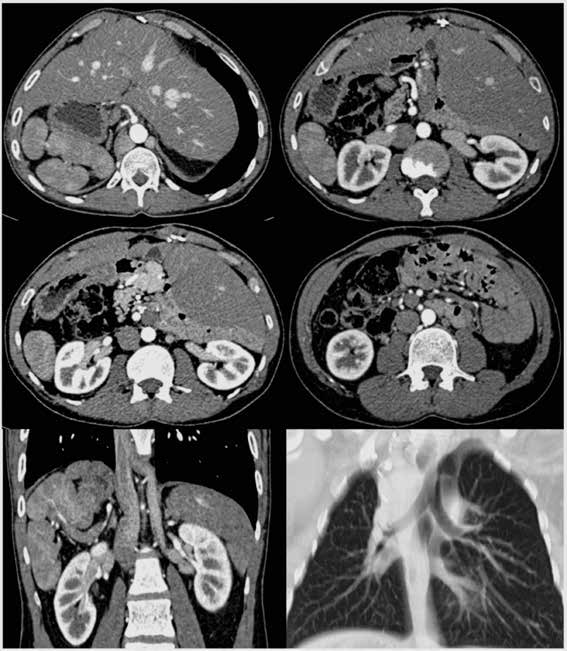

Homme de 30 ans. Bilan pré-opératoire d’une cardiopathie congénitale. Pas d’autre antécédent connu. Aucune symptomatologie abdominale. Sur ces images TDM acquises au temps artériel après injection de produit de contraste iodé (figure 1), vous retenez le(s) diagnostic(s) de :

Le diagnostic est celui d’un situs inversus incomplet (aussi appelé situs ambigus) dans le cadre d’un syndrome d’hétérotaxie avec polysplénie : les réponses A, B, E sont correctes.

Deux observations écartent l’hypothèse d’un situs inversus complet : la position habituelle du couple aorte - VCI et l’isomérisme (symétrie droite/gauche) de l’arbre trachéo-bronchique. Le situs solitus correspond à une répartition normale des structures anatomiques.

Analyse sémiologique du cas présenté

- Arbre trachéo-bronchique : isomérisme avec « deux poumons gauches » (bilobés, absence de la division précoce de la bronche lobaire supérieure droite).

- Foie : inversé et médian, avec un « lobe gauche » à droite et « un lobe droit » à gauche.

- Vésicule biliaire : médiane.

- Pancréas : inversé, court (ou tronqué).

- Rate : inversée avec polysplénie.

- Dextrogastrie.

- Tube digestif bas : colon à droite, grêle à gauche, mésentère commun complet inversé.

- Aorte : à gauche, position normale.

- Veine cave inférieure : position normale à droite, mais agénésie segmentaire en rétrohépatique, avec continuation hémi-azygos.